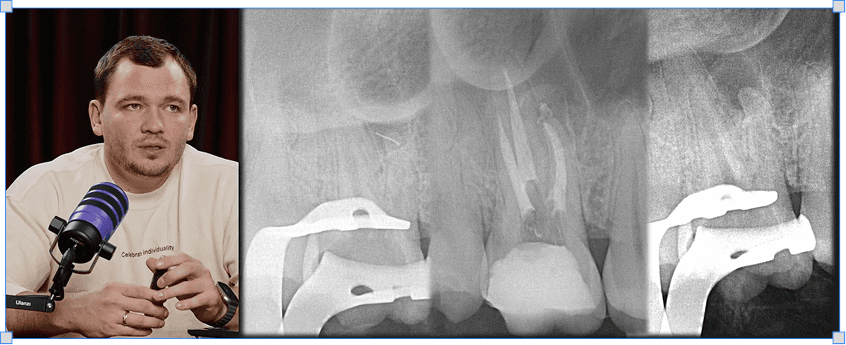

Микола Сорухан

Повторна ендодонтія

4 модулі

3 години

Все про штифти і розпломбування при повторному ендо

Протоколи вилучення уламків зламаних інструментів

Протоколи роботи зі сходинками і перфораціями в каналах